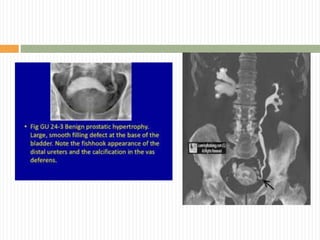

 Pemeriksaan radiologis

 Foto polos abdomen  batu, pembesaran

ginjal atau buli-buli. Dapat juga dilihat lesi

metastasis dari keganasan prostat

 IVP fungsi renal, hidronefrosis dan hidroureter,

fish hook appearance (gambaran ureter berbelok-

belok di vesika). divertikel, residu urin, atau filling

defect di vesika.